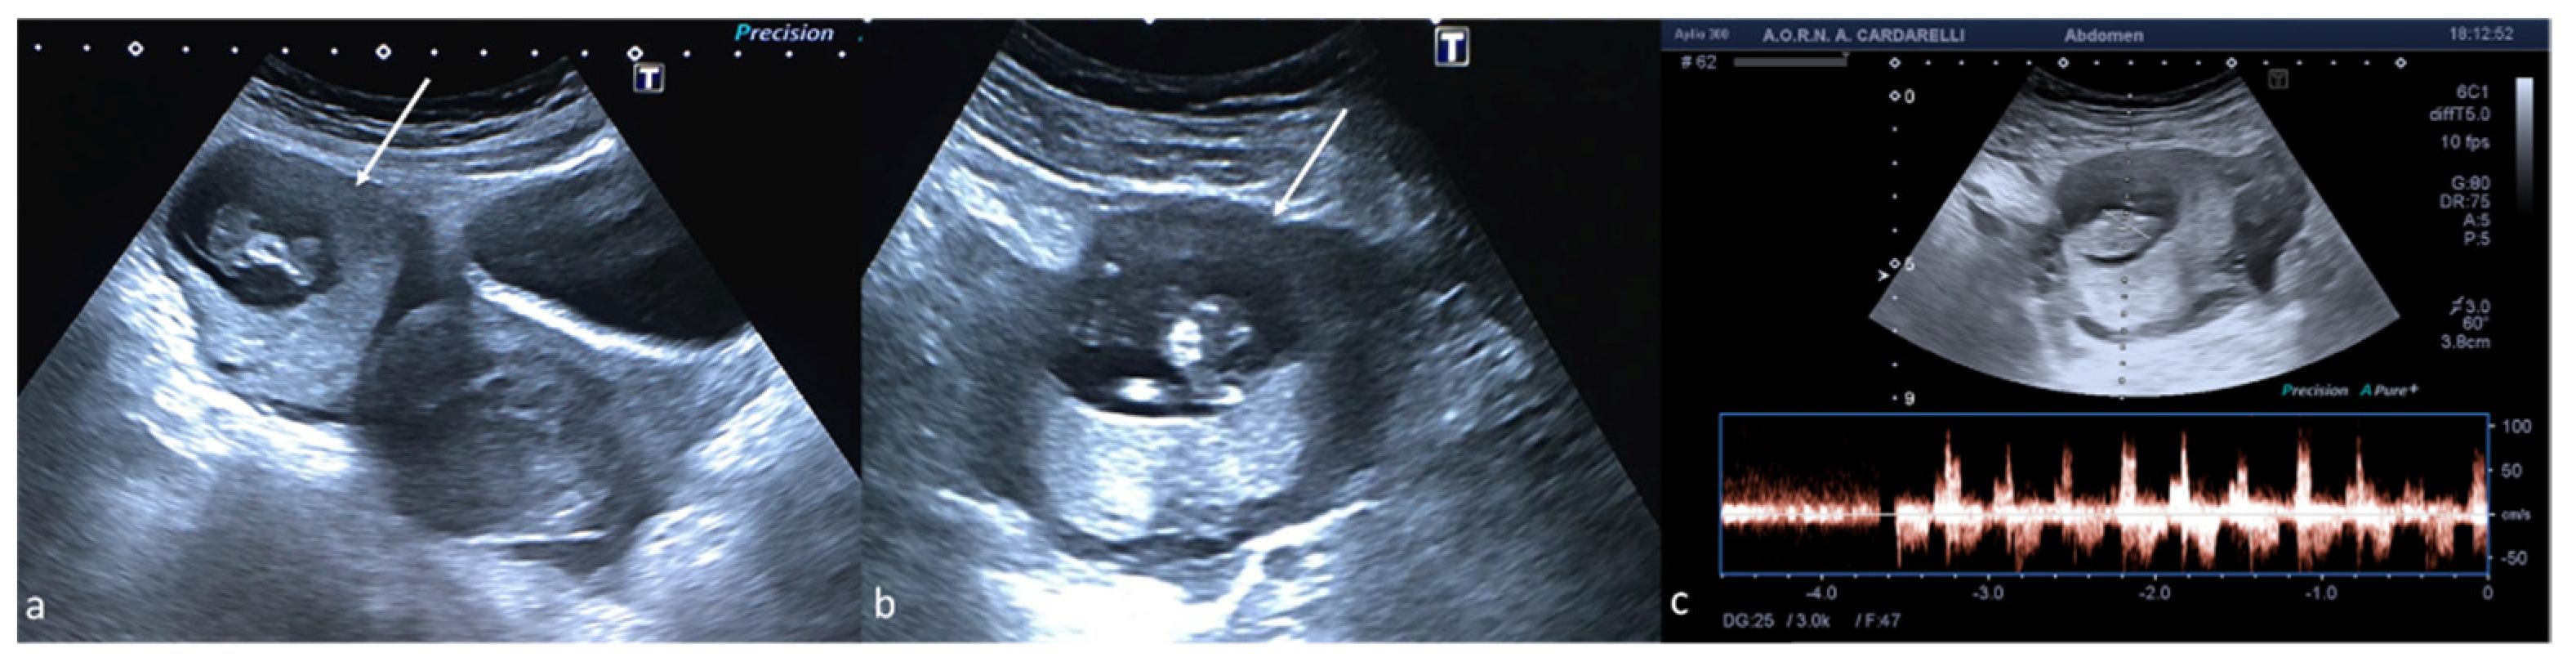

Figure 12. Ectopic pregnancy. Axial (a) and longitudinal (b) TSA–US scans reveal an extrauterine adnexal gestational sac with a fetal body ((a,b), arrow). On pulsed Doppler (c) a heartbeat is also detected.